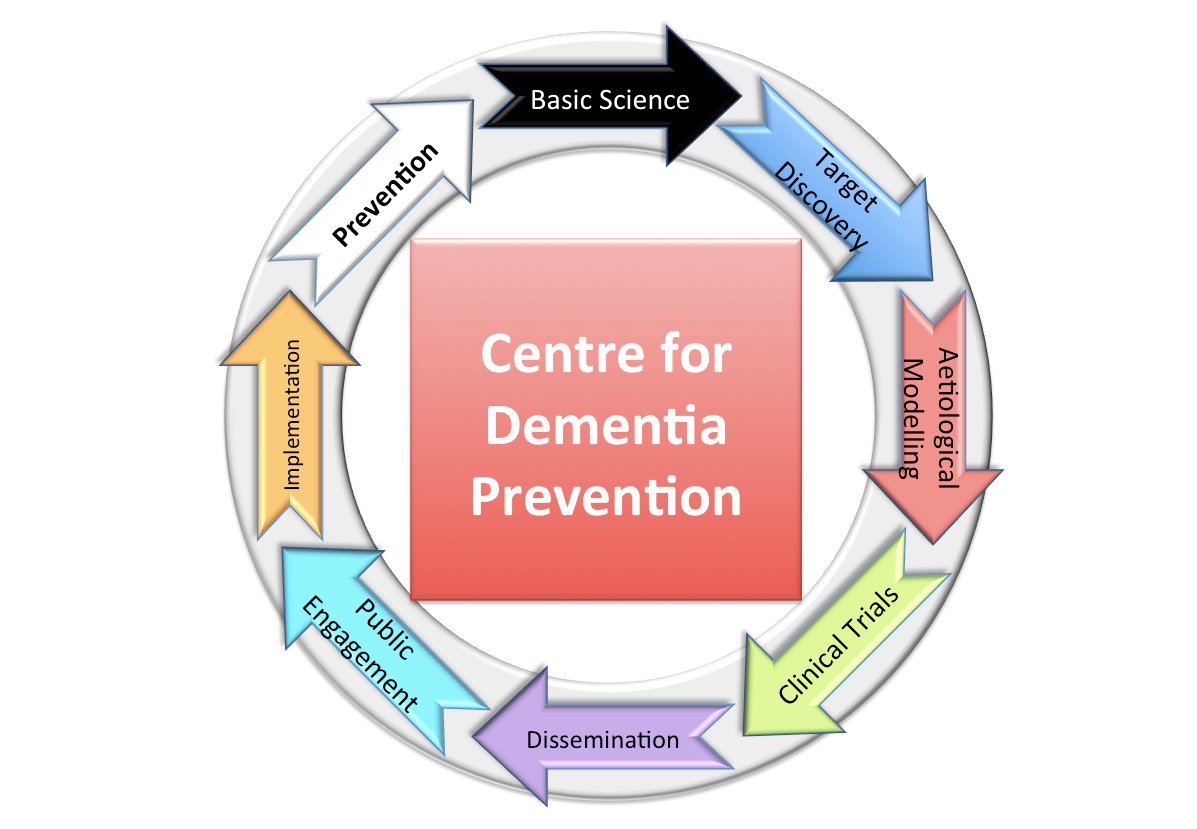

The Centre for Dementia Prevention brings together three research domains under one umbrella organisation, each critical in achieving dementia prevention.

Basic Science and Drug Discovery:

First we need to have the deepest understanding of neurodegenerative disease especially in the period before dementia develops. In doing so, we can help understand the reasons people get dementia we when the diseases are at the earliest phase, we can work out how best to test people for these conditions and ultimately we can develop rational targets for drug development and ways to measure the success of these drugs.

Clinical Science (Epidemiology and Trials):

Once we have the necessary knowledge of disease, we have to translate these findings into the clinical environment by undertaking trials. The epidemiological work at population levels also helps elucidate associations between risks and disease which provide the basic scientists pointers to where to look for the biological plausibility linking genetic, environmental and clinical risks to dementia.

Social Science and Public Health:

Prevention can also be applied to people who have developed dementia as we seek to understand how we can prevent moving from early stages of dementia to later stages – this attempt to prevent impairment becoming disability

underpins our tertiary prevention work which will also benefit from greater understanding disease processes and high quality trials to test interventions. This domain will also focus on getting research into practice so that earlier work is informed by the likelihood of acceptability to the public and policy makers. It will also though work on influencing policy makers and the pubic to ensure that effective prevention strategies can be implemented seamlessly and rapidly.

The strength of CDP is that each of these domains are merged under one organisational structure creating a single knowledge and scientific platform with the singular objective to prevent dementia. Basic science must be aware of what is feasible at a population level and the social scientists must be ‘ahead of the curve’ for what is in the pipeline in terms of tests and interventions. The clinical scientists provide the epidemiological and human proof of biological discovery and help translate and modify this science in line with social and public demands.